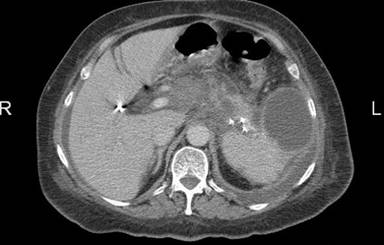

A 75-year-old woman presented with a three-month history of abdominal pain radiating to the back, nausea, vomiting and weight loss. Her past history was unremarkable except for diabetes of 5 years duration which was regulated with diet alone. Her laboratory tests upon admission were as follows: white blood cell count 20,700 mm-3 (reference range: 4,000-11,000 mm-3), hemoglobin 8.5 g/dL (reference range: 11.7-15.5 g/dL), lactate dehydrogenase 501 U/L (reference range: 240-480 U/L), glucose 216 mg/dL (reference range: 70-110 mg/dL), total protein 5.95 g/dL (reference range: 6.4-8.3), albumin 2.6 g/dL (reference range: 3.4-4.8 g/dL), beta-2-microglobulin 10,355 ng/mL (reference range: 609-2,366 ng/mL). The tumor marker levels of AFP, CEA; CA 125, CA 15-3 and CA 19-9 were all within the normal range. Abdominal computed tomography (Figure 1) revealed a mass in the pancreatic tail which could not be distinguished from the pancreas parenchyma and nearby surrounding soft tissues, with encasement of the splenic artery and vein, accompanied by splenic infarct and lymphadenopathies located at the portal hilus, para-aortic region and left renal hilus. To differentiate the origin of the pancreatic mass as an endocrine or an exocrine tumor, serotonin, 3-methoxytiramine, metanephrine, normetanephrine, vanyl mandelic acid, 5 hydroxy indole acetic acid and dopamine tests were performed and were found to be within normal levels. Percutaneous ultrasonography-guided biopsy of the suspicious peripancreatic node confirmed the diagnosis. Immunohistochemical studies of the biopsied tissue demonstrated large atypical lymphoid cells which were positive for CD20 with a Ki-67 index of 30%. The final diagnosis was diffuse large B cell lymphoma. Bone marrow aspiration and biopsy did not show any involvement of disease.

Figure 1. Abdominal computed tomography shows a mass of the pancreas invading the nearby surrounding soft tissues. |